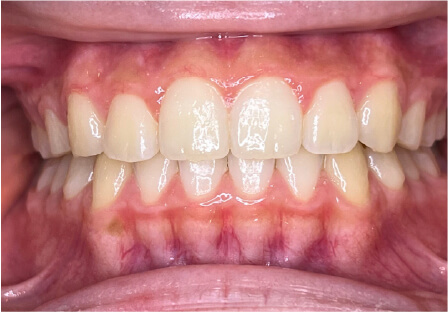

叢生の症例

13歳

男性

相談内容

マイオスマイルからの移行

カウンセリング・診断結果

治療内容・方法

全額アライナー矯正

術後の経過・現在の様子

クリアライナー使用

治療のリスク

痛み・歯根吸収・歯肉退縮・虫歯・後戻り

費用・治療期間

(インビザのみ)745,000円、1年11ヶ月